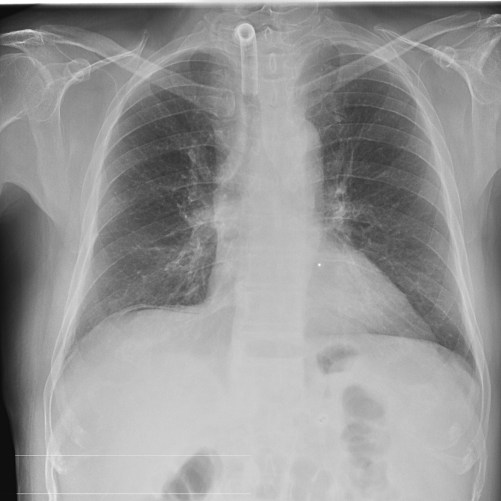

CASO: Febrícula y tos de 4 días de evolución.

Hallazgos:

- En la placa PA se observa una asimetría en los hilios pulmonares, el hilio izquierdo tiene una densidad aumentada.

- Tras examinar la placa lateral se observa un aumento de densidad en la columna que puede ser compatible con una condensación, es el signo de la desnificación vertebral.

SIGNO DE LA DENSIFICACIÓN VERTEBRAL: En la radiografía lateral normal, la densidad de la columna torácica tiende a disminuir desde la parte superior hasta el diafragma; la alteración de ese patrón por la presencia de una densidad superpuesta a la columna, indica la existencia de una consolidación pulmonar. Este signo adquiere especial valor cuando en la proyección posteroanterior la consolidación está oculta en el espacio retrocardíaco o en la base pulmonar.